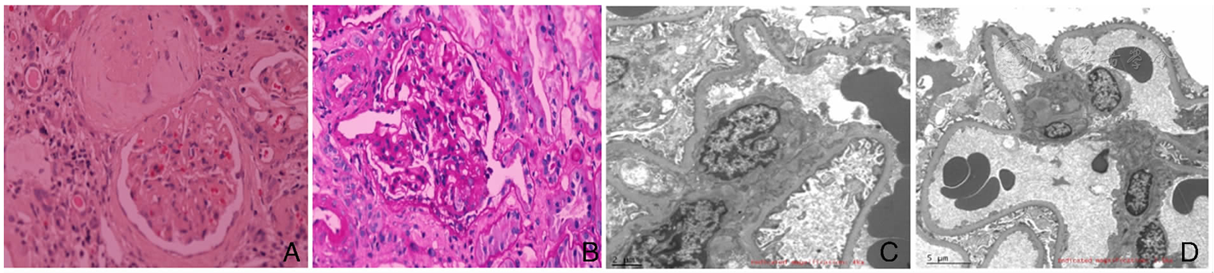

图1

患者的肾小球光镜、电镜检查

注:A:肾小球球性硬化(苏木精-伊红染色×400);B:肾小球节段性硬化,节段性硬化区域位于尿极处伴周边脏层细胞肥大(过碘酸-雪夫染色×400);C:系膜细胞和基质轻度增生,肾小球各部位未见确切电子致密物沉积(电镜×4 000);D:肾小球足细胞足突大部分融合(电镜×2 500)